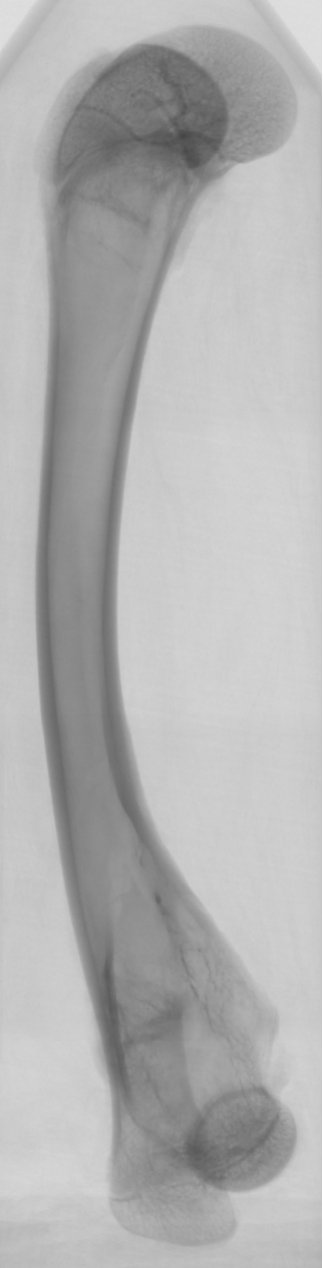

骨骼組織的三維重建

顯微 CT 可以以非破壞性的方式對骨骼組織進行三維成像,包括骨小梁的連通情況、骨密度分布等信息。這為人工骨骼的設計與制備提供了關鍵的參考,也可用于研究骨骼力學特性及其在仿生工程中的應用。